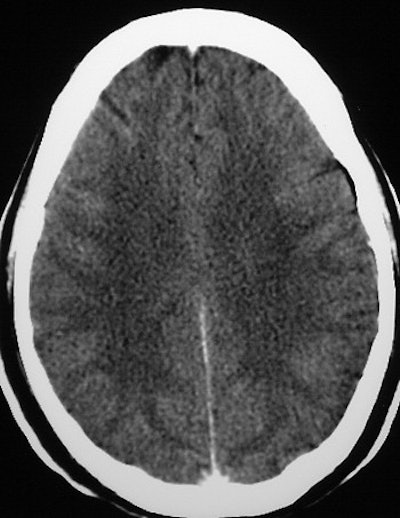

Axial cuts at the levels of the lateral ventricles and centrum semiovale (mAs 335, kv 120). A loss of GWMD is shown in a 51-year-old comatose patient with exertional HS in comparison to good GWMD in a 50-year-old patient, below. Images courtesy of Dr. Oded Szold.

According to the results, "all six patients demonstrated severe loss (grade 2-3) of the GWMD. None suffered from CNS bleed or displacement of anatomical structures. The difference on CT between the gray and the white matter is thought to be due to the higher content of water and lower content of lipids in the gray matter. This results in higher oxygen and lower carbon concentrations in the gray matter, causing increased photoelectric absorption," they said.